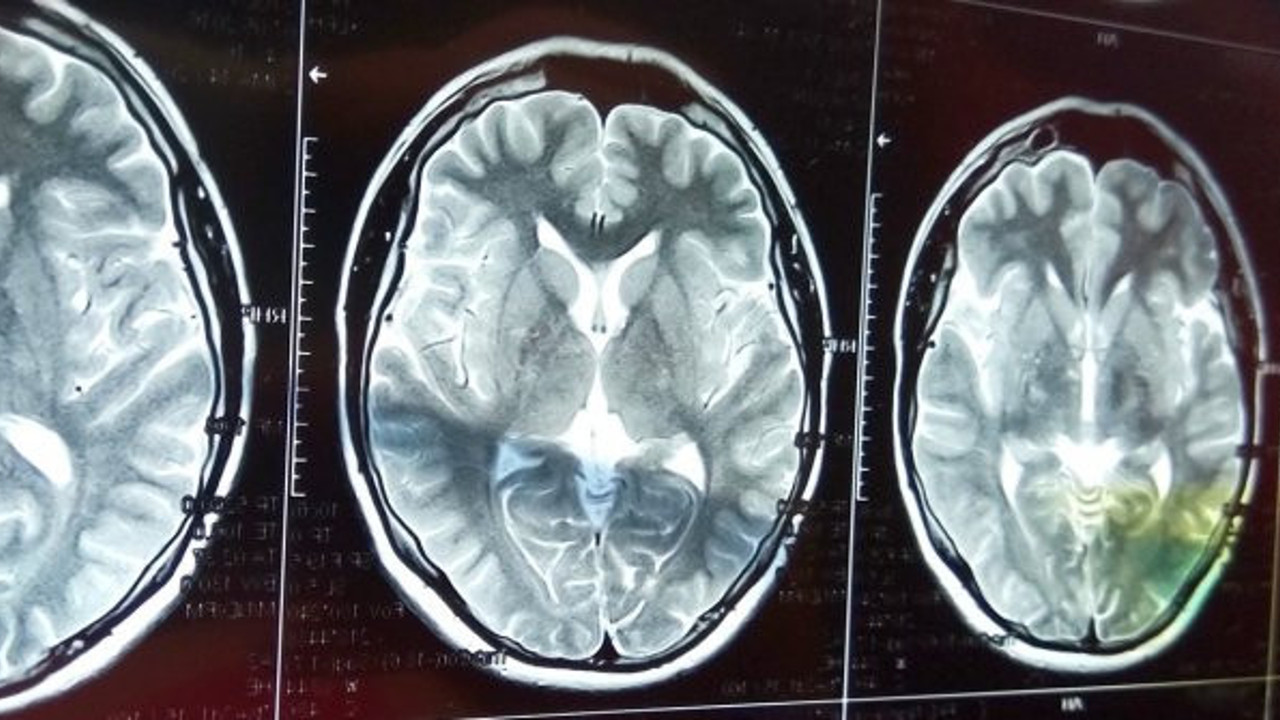

Londra Üniversitesi Nöroloji Enstitüsü’nde danışman Dr. Michael Zandi, birkaç aydır bu bulgulardan şikayet eden hastalar gördüğünü bildirdi. Vücuttaki iltihaplanmadan, beyindeki oksijen eksikliğine kadar birçok faktörün Covid-19 hastalarında bu tür belirtilere neden olacağını vurgulayan Dr. Zandi, özellikle yoğun bakımda fazla vakit geçiren Covid-19 hastalarında psikolojik faktörlerin de yer alabileceğini vurguladı.

Amerikan Klinik Nöropsikoloji Akademisi’nin eski başkanı Dr. Wilfred Van Gorp, Covid-19’u atlatan birçok hastada "beyin sisi"nin yanında baş ağrılarından, yüksek ses tahammülsüzlüğüne ve duyguları kontrol etme güçlüklerine kadar geniş bir yelpazede sorunlar gördüğünü söyledi. Ayrıca Van Gorp, “bu şikayetlerin beyin sarsıntısı sonrası hastaların şikayetlerine oldukça benzediğini” vurguladı.

Paterson ve meslektaşları gibi diğer araştırmacılar da nörolojik semptomlarla hastaneye kaldırılan ve bu semptomlara sahip olmayan Covid-19 hastalarından toplanan kan ve omurilik sıvılarını inceliyor. Bu çalışmanın amacının, nörolojik semptomları olmayan hastaların nörolojik hasar görüp görmediğini öğrenmek olduğu belirtildi.